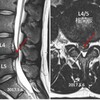

大腿骨寛骨臼インピンジメントとは以下のように定義されています。(Griffin et al. BJSM. 2016)

- 股関節の動きに関連する障害

- 症状と臨床所見と画像所見の3つを伴う

- 大腿骨と寛骨臼の早期衝突を生じ,痛みなどの症状がある